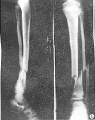

胫腓骨骨折